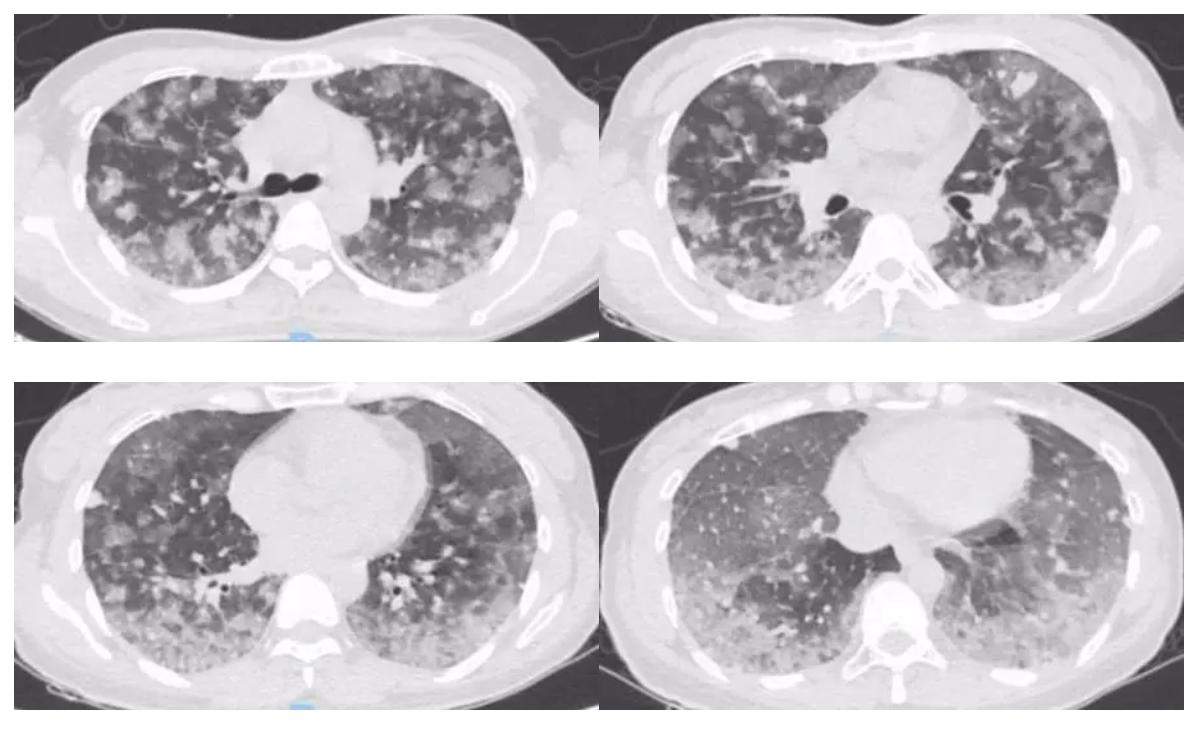

复查胸部CT:

黄国鑫主任(影像科)点评:

与前两次CT对比第三次胸部CT提示肺部病变继续进展,肺部多形性结节部分融合,肺部磨玻璃渗出较前进展,但所有叶间胸膜、小叶间隔、中轴间质都无明显改变,小叶间隔无结节样改变,最早胸部CT即尚无明显弥漫肺泡出血时的表现双肺结节呈血行分布,另呈不同阶段结节,除血行分布,可见胸膜结节,这种情况用小血管炎、肉芽肿性血管炎不好解释。随着病情进展,第二次胸部CT还有一个特点就是双肺结节呈中央致密、周围磨玻璃样渗出,当时考虑血管炎、感染性疾病如真菌、结核等,但血行播散肺结核一般呈三均匀:分布均匀、大小均匀、密度均匀,结合临床基本排除。影像方面肿瘤首先考虑转移瘤,不支持点为转移瘤一般表现边缘光滑,但该患者结节边缘模糊渗出,不是典型的转移瘤征象。但综合患者肺部病变血行分布、胸膜分布、进展迅速,需考虑肿瘤性病变肺内转移。结合病史注意有无其他部位原发肿瘤。另CTPA未见肺动脉充盈缺损。